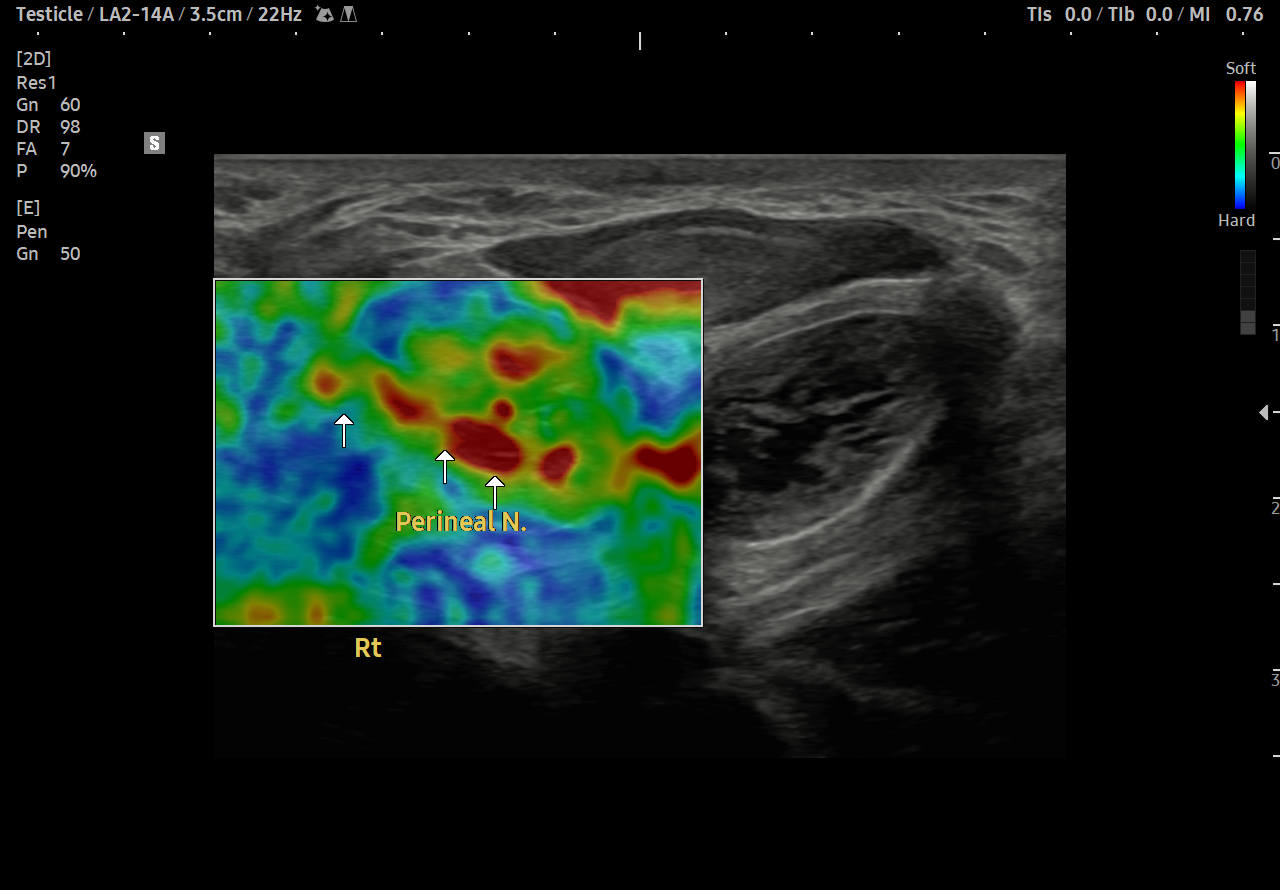

통증 부위를 살펴볼까요?

회음부의 통증과 치골부위 통증이 심했습니다.